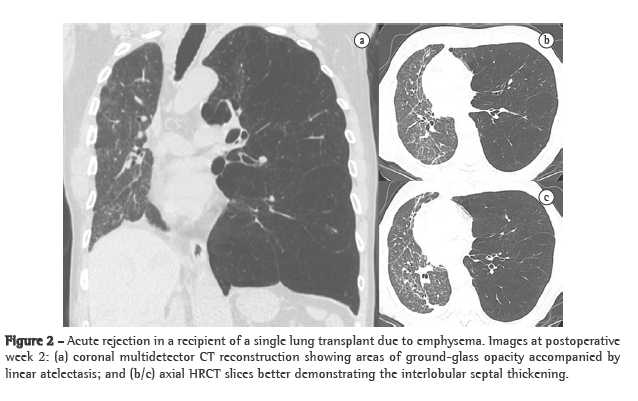

Acute rejectionAcute rejection after transplantation is a common occurrence. Nearly 95% of patients present at least two episodes within the first month after surgery. Histologically, acute rejection is characterized by predominantly lymphocytic perivascular infiltrate, with or without bronchiolar involvement.(8) Symptoms are generally nonspecific, including low-grade fever, breathlessness and fatigue. Most patients experience at least one episode of acute rejection within the first 3 weeks and remain at high risk for this complication for the first 100 days after transplantation.(5) Chest X-ray findings are normal in up to 50% of cases.(6) The most common findings are perihilar and lower-lobe opacities, as well as interlobular septal thickening and pleural effusion (Figure 2).(9) The HRCT features are relatively nonspecific and include ground-glass opacities (often with basal distribution), peribronchial cuffing, septal thickening (interlobular and intralobular) and new or more extensive pleural effusion.(10) This complication can be almost completely excluded if there are no ground-glass opacities.(9) Acute rejection is treated with intravenous corticosteroids and typically responds quite well after 24 h of this treatment. A dramatic reduction in abnormal radiological features after 48 h of intravenous administration of methylprednisolone is indicative of a diagnosis of acute rejection.(9,10)